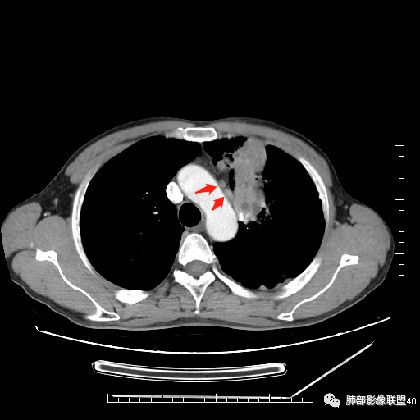

左上肺占位支气管阻塞伴肺不张、肿瘤不均匀强化,考虑鳞癌.

左肺上叶见实性结节,边缘可见分叶,周周可见磨玻璃影,病灶不均匀强化,中心可见坏死,部分坏死边界不清,部分呈环形,血管进入病灶内部,边缘逐渐变细截断,总体表现考虑恶性,腺癌。

中年男性,咳嗽咳痰一月。左肺上叶团块状软组织密度影,边缘部分清晰周围见磨玻璃影,增强后其内密度不均可见散在斑片状低密度区,血管造影征完整,团块邻近胸膜可见多发圆形低密度透光灶。左肺门处上叶血管似被包绕。左侧胸膜粘连肥厚。考虑1.左肺占位,淋巴瘤?鳞癌?2.因病灶内散在低密度待除外感染性病变可能

中年男性,咳嗽咳痰一月余入院胸CT:左肺上叶前段占位性病变,病灶内可见密度不均,可见低密度区,病灶可见分叶,增强病灶内可见血管征,血管边缘模糊,病灶近胸膜下呈膨胀性生长。诊断考虑:恶性病变。

40岁以上男性,中等病程,咳嗽,咳痰,左上块影,孤立,膨胀,胸膜受累,内密度高低不一,血管穿入,考虑肺癌,鳞?气管镜or穿刺!

左肺上叶肿块,强化不均匀,内见坏死,血管纤细,病灶周围有阻塞性炎,所见图像未见肿大淋巴结。考虑鳞癌可能大。

中年男性,亚急性起病,咳嗽,咳痰,左肺上叶肿块,边界清,膨隆,可见分叶,增强可见内部坏死,不均匀强化,部分边界累及胸膜,考虑恶性。

左肺上叶肿块,周周可见磨玻璃影,不均匀强化,内部可见坏死,部分坏死边界不清,血管进入病灶内,恶性肿瘤,考虑鳞癌。

分叶,破坏力不强,纵隔胸膜受累,周围阻塞性炎症,胸膜多发结节。考虑恶性,支持腺癌可能大。

左肺上叶肿块,边缘大部分平直,部分膨隆,周周可见磨玻璃影,不均匀强化,内部可见坏死,部分坏死边界不清,考虑恶性肿瘤,鳞癌可能大,病灶边缘大部分平直,不除外炎性。

患者中年男性,咳嗽、咳痰1月余入院。胸部CT:左肺上叶尖段近胸膜下肿块占位灶,边缘光滑,边界清楚,周围可见片状磨玻璃影,可见平直、毛刺、分叶征象,增强轻度强化,内可见点片多发低密度区及部分血管影,与支气管关系欠清,左肺上叶背侧胸膜增厚、胸膜下结节,右肺似见多发小结节灶,淋巴结不大。综合考虑良性病变,结核可能性大,鉴别腺癌并肺内、胸膜转移及淋巴瘤等。

左肺上叶见不规则肿块影,可见分叶,边缘膨隆部分边缘平直,增强后病灶可见不均匀明显强化,内见血管影,其血管边缘不光滑,周围肺野可见小结节病灶,考虑恶性病变,肿块与支气管关系显示不清,需要薄层,从肿块边缘平直来看应该有阻塞性肺炎和肺不张,偏向鳞癌。

男性,47岁,咳嗽咳痰一月。

胸CT:左上叶前段团块影,边缘部分清晰,近纵隔侧膨隆明显,分叶,肺侧见平直征,U形凹陷,病灶周围可见磨玻璃影,气肿带,纵隔多发淋巴结肿大,叶间裂多发小结节。增强病灶内密度不均,散在斑片状低密度区,血管造影征。考虑:恶性,鳞?腺?大细胞?鉴别:炎症。似有左侧胸廓内A供血病灶,SFT?